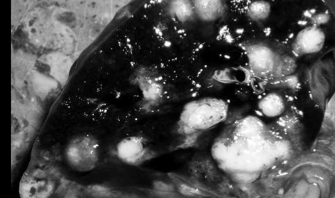

Francisella leads to a ______ inflammation in the liver, spleen, and lymph nodes

pyogranulomatous

Tularemia looks similar to _____ because it causes abcesses within the _____

tuberculosis

causes abscesses within the lungs